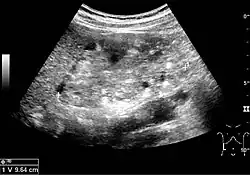

The kidney is divided into parenchyma and renal sinus. The renal sinus is hyperechoic and is composed of calyces, the renal pelvis, fat and the major intrarenal vessels. In the normal kidney, the urinary collecting system in the renal sinus is not visible, but it creates a heteroechoic appearance with the interposed fat and vessels. The parenchyma is more hypoechoic and homogenous and is divided into the outermost cortex and the innermost and slightly less echogenic medullary pyramids. Between the pyramids are the cortical infoldings, called columns of Bertin (Figure 1). In the pediatric patient, it is easier to differentiate the hypoechoic medullar pyramids from the more echogenic peripheral zone of the cortex in the parenchyma rim, as well as the columns of Bertin (Figure 2).[1]

Figure 1. Normal adult kidney. Measurement of kidney length on the US image is illustrated by '+' and a dashed line. *Column of Bertin; ** pyramid; *** cortex; **** sinus.[1]